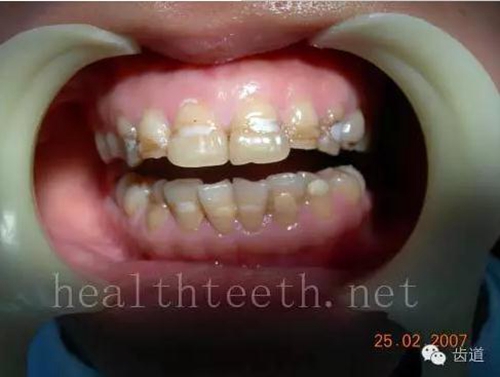

18歲孩子的口腔狀況